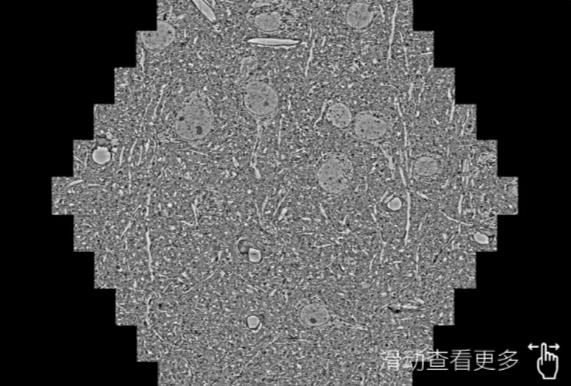

鼠脑切片。左图使用江北蔡司江北扫描电镜MultiSEM706对165μmx143pm面积区域成像,耗时仅需1.5秒。右图为鼠脑切片中30μm区域放大效果。样品由芝加哥大学B.Kasthuri提供。

使用蔡司高速江北扫描电镜MultiSEM对1mm²人脑皮层组织进行高分辨成像,并对其中的各种细胞结构进行三维重构分析。左图展示了2x3mm²组织平面中锥体神经元的三维重构效果。右图显示了局部体积神经元三维重构。图像由哈佛大学chtman实验室提供,渲染图由D. Berger 制作。